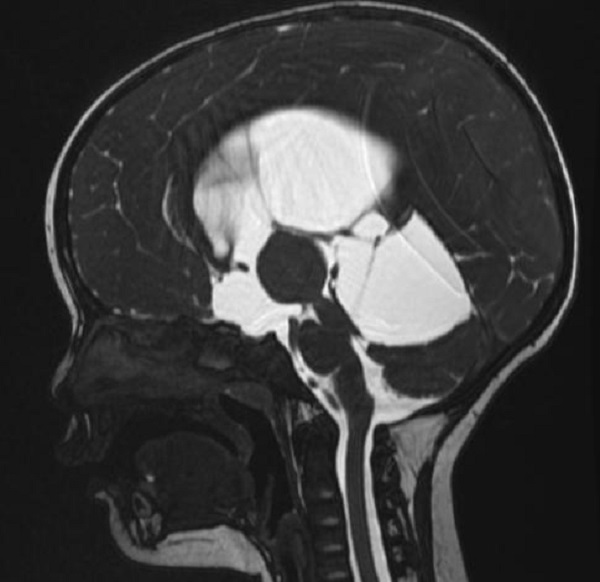

一岁多的赫赫小朋友自出生头颅就比同龄小孩大,近半月来进食后出现呕吐,伴头痛,在当地医院及省内多家医院治疗不见好转,于是来到陕健医二一五医院神经重症监护室,因患儿近半月多不能正常进食,入院时精神萎靡,头颅MRI检查提示“脑室系统扩大,双侧脑室额角周围间质水肿,左侧丘脑占位病变,鞍上池及小脑上池扩大”。

为进一步鉴别脑积水类型,行磁共振3D FIESTA序列检查可见侧脑室扩大明显,中脑导水管中段阻塞、三脑室底受压下陷,诊断梗阻性脑积水。